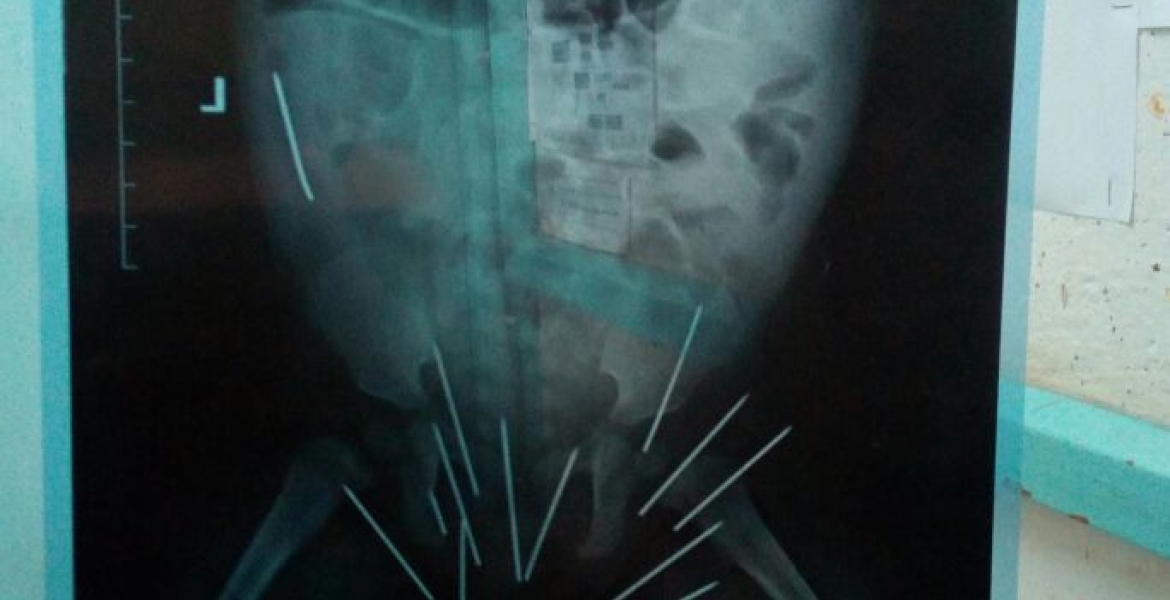

Doctors at Thika Level 5 Hospital have successfully removed 13 sewing needles from a 10-month-old baby.

31-year-old Ndunge informed the doctors of the needle after the baby was admitted at the facility with Pneumonia. She was referred for an Xray, which revealed 14 needles in her body.

Medics the carried out an emergency surgery and removed 13 needles, but one was left because it had penetrated to the hip bone and needs specialized attention to extract. Kiambu County Chief Officer in charge of Health Andrew Toro, said removing the remaining needle could damage the baby's tissues as it is lodged too deep inside one of the bones.